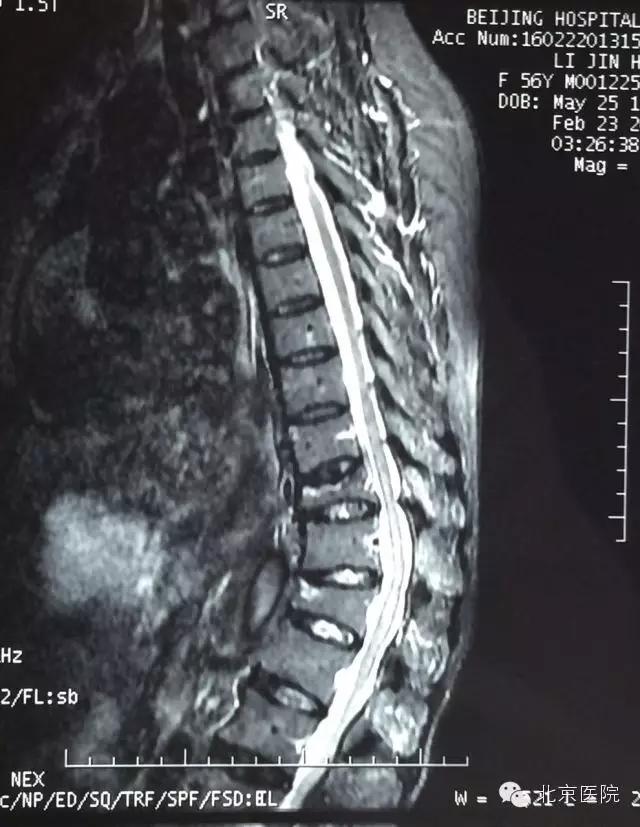

3月中旬,来自河北省大城县的56岁的李女士,十几年前的外伤导致了她胸椎骨折,在当地落后的医疗条件下,采取保守治疗后患者有两节椎体变形,慢慢的使得患者像个80多岁的老年人一样,弯了腰驼了背。多年来腰背痛一直伴随着李女士,并且逐渐加重,导致她日常生活、活动能力都严重受损。她不但不能像正常人一样劳动,还成为了家庭的负担,使得患者整个家庭都陷入了痛苦。后来经人介绍,患者在家属的陪同下来到了北京医院骨科,就诊于孙常太副主任的门诊。经过仔细的查体和评估,诊断为胸腰椎后凸畸形、重度骨质疏松症,孙常太副主任将患者收入院并准备手术治疗。

在完善了术前检查后,经过骨科全科专家会诊、脊柱组组内讨论后,制定了适合该患者的详细手术方案。通过术前测量,该患者的后凸畸形成角角度约60°,由于骨折后楔形变的胸12椎体前缘高度下降太多,导致脊柱后凸的顶点位于胸12椎体,故采取了经胸12椎弓根椎体截骨矫形手术。这种手术通过将变形的椎体截去三角形的一部分,把椎体后缘的高度降低到跟前缘一样,从而把后凸变形的脊柱“掰直”,然后通过椎弓根钉棒系统牢牢地将脊柱固定在符合生理力线的位置上,有效的缓解了胸背部的肌肉张力,从而大大缓解了患者的腰背部疼痛。该手术由孙常太副主任、申剑副主任医师、王强副主任医师等组成的治疗组实施,在手术麻醉科的喻震、郭晓曦等同仁的全力配合下,术中精心操作,小心避开了极易损伤的脊髓圆锥部分,顺利的完成了截骨、矫形、固定等步骤。术后该患者在骨科高凡护士长带领的优秀护理团队的精心照料下,安全康复,术后第6天即下地活动,下肢神经功能完全正常,腰背部疼痛得到了明显地缓解,并于术后第9天顺利出院回家。